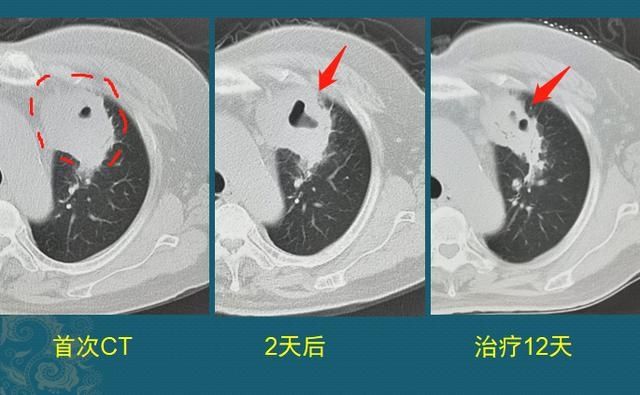

所以金葡菌肺炎的进展期CT征象可以一日内就发生变化,如下图

这类感染开始时比较含蓄,小贪官嘛,先伪装成低毒力的老实人,只引起较轻的细支气管周围炎症。但如果不及时使用敏感抗生素,这种细支气管周围炎会快速进展为小叶、亚段或肺段的实变区,呈融合的斑片状,支气管远端常不显示(被脓液堵塞),然后实变区中央的肺组织会很快发生坏死、液化、经支气管排出脓液后就形成了空洞:

周围脓肿壁血管丰富,增强扫描呈现明显均匀强化,这个可以鉴别肺癌(肿瘤形态变化慢,多为轻度不均匀强化;结核是亚急性炎症,变化也没这么快!)

下图这一例金葡菌肺炎,因为及时抗菌治疗,终止了腐败,挽救了肺组织,7天后明显好转: